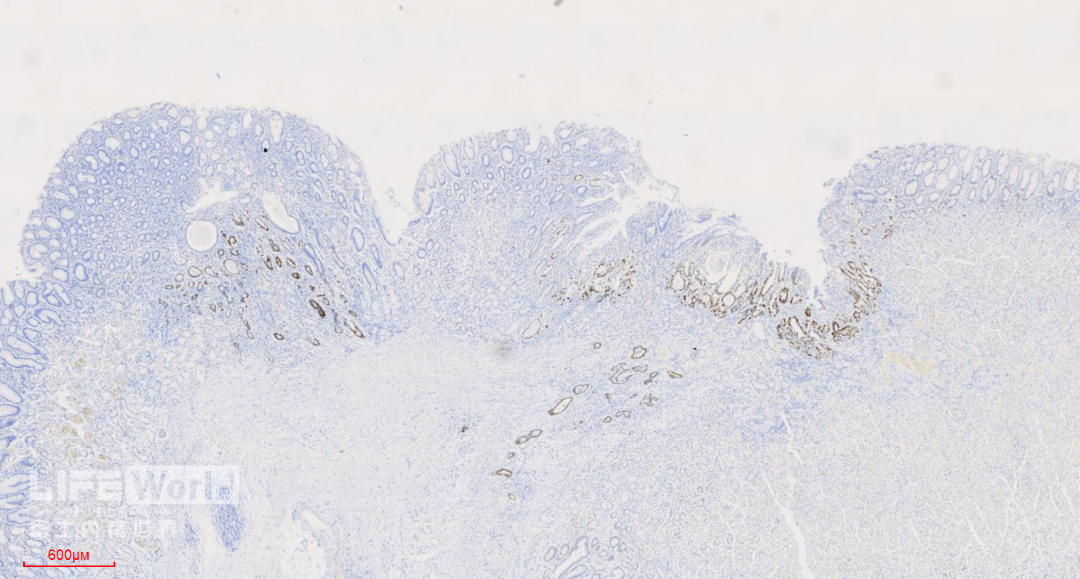

HE染色:2号切片示中分化腺癌,6号切片示高级别上皮内瘤变,局灶癌变。

富士胃镜英文怎么写病例分享 | 周环:一例不易判断的胃体病变的诊治分享(富士内镜早癌读片会)_https://www.jmylbn.com_新闻资讯_第40张

富士胃镜英文怎么写病例分享 | 周环:一例不易判断的胃体病变的诊治分享(富士内镜早癌读片会)_https://www.jmylbn.com_新闻资讯_第41张

这是2号切片,病变位于一条皱襞顶端。

富士胃镜英文怎么写病例分享 | 周环:一例不易判断的胃体病变的诊治分享(富士内镜早癌读片会)_https://www.jmylbn.com_新闻资讯_第42张

病变处(红圈内)可见不规则的腺管状结构,部分呈筛网状。图中可以看出,病灶间可见相对正常的胃底腺结构。图片中最深的病灶已经侵及粘膜肌层。

富士胃镜英文怎么写病例分享 | 周环:一例不易判断的胃体病变的诊治分享(富士内镜早癌读片会)_https://www.jmylbn.com_新闻资讯_第43张

病变处细胞异型性明显。病变内部可见多处扩张的腺管,内部可见坏死碎片。对应胃镜图片上的白色球状物。

富士胃镜英文怎么写病例分享 | 周环:一例不易判断的胃体病变的诊治分享(富士内镜早癌读片会)_https://www.jmylbn.com_新闻资讯_第44张

富士胃镜英文怎么写病例分享 | 周环:一例不易判断的胃体病变的诊治分享(富士内镜早癌读片会)_https://www.jmylbn.com_新闻资讯_第45张

此为病变最深的地方,癌变的腺管侵及粘膜肌层。

富士胃镜英文怎么写病例分享 | 周环:一例不易判断的胃体病变的诊治分享(富士内镜早癌读片会)_https://www.jmylbn.com_新闻资讯_第46张

富士胃镜英文怎么写病例分享 | 周环:一例不易判断的胃体病变的诊治分享(富士内镜早癌读片会)_https://www.jmylbn.com_新闻资讯_第47张

CK-pan染色显示肿瘤细胞为上皮细胞,呈不规则腺管状排列,提示为中分化腺癌。